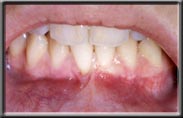

A lack of attached gingiva is sometimes associated with a high frenum attachment, which exaggerates the pull on the gum margin. A frenum is a naturally occurring muscle attachment, normally seen between the front teeth (either upper or lower). It is normal to have a frenum, but it should not pull on the gum margin or recession will occur. If pulling is seen, the frenum is surgically released from the gum with a frenectomy. Often a new band of hard gum is also added to re-establish an adequate amount of attached gingiva (see below).